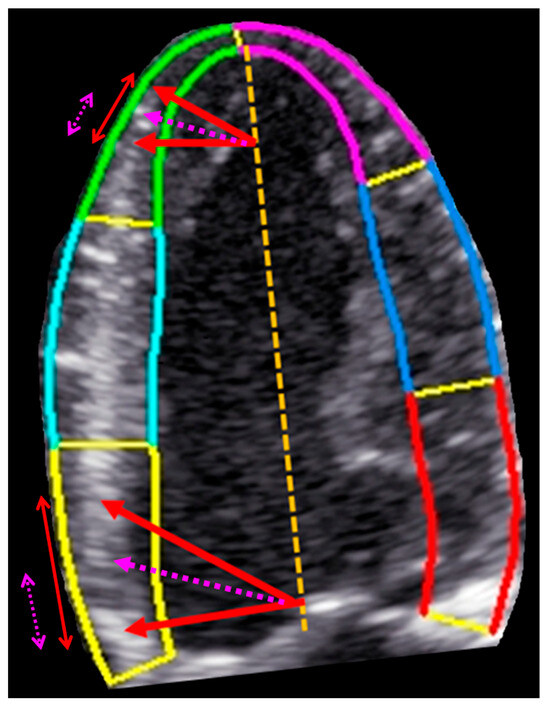

Echocardiography remains a cornerstone of contemporary cardiac imaging, offering a versatile, noninvasive, and widely accessible tool for the diagnosis, risk stratification, and management of cardiovascular diseases. Continuous technological advancements—including speckle-tracking echocardiography, three-dimensional imaging, the application of artificial intelligence, and integration with multimodality imaging—have significantly expanded its clinical capabilities.

This Special Issue aims to highlight recent advances and emerging clinical applications of echocardiography across a broad spectrum of cardiac conditions, including ischemic heart disease, cardiomyopathies, valvular heart disease, heart failure, and atrial pathology. Original research articles, state-of-the-art reviews, and clinically focused studies addressing novel echocardiographic parameters, methodological validation, prognostic implications, and practical implementation in routine clinical practice are particularly encouraged.